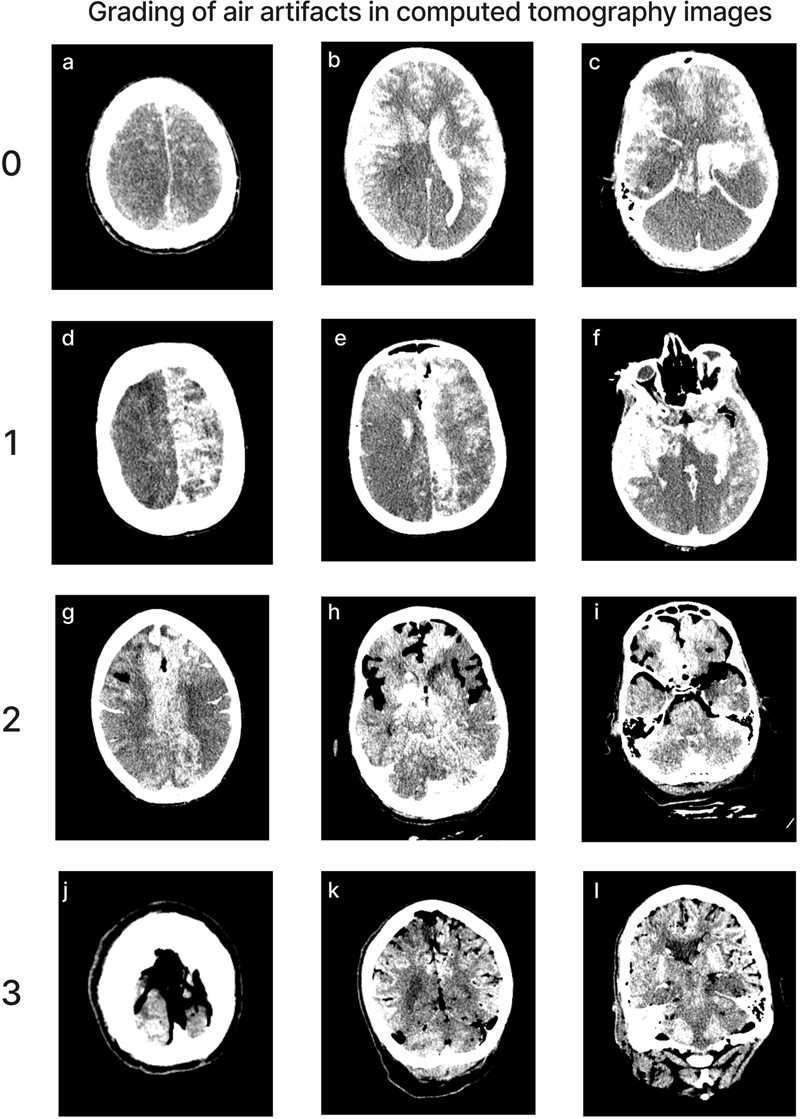

Quality of perfusion in CT images

Perfusion quality based on CT scans was graded on a semi-quantitative scale, reflecting the estimated percentage of contrast agent present in different brain regions (Figure 4). We also developed a semi-quantitative grading scale to assess the extent of air bubbles observed in some CT scans (Figure 5). For a subset of cases, the images were graded separately by two independent raters, yielding an ICC of 0.536 (95 % CI: 0.293–0.705), indicating fair interrater reliability. Consistent with the observations from gross examination images, the CT scans revealed patchy distribution of contrast in nearly all cases, both across and within vascular territories.

Figure 4.

Representative images of CT scans that demonstrate the grading schema. All images show the grading for both the left and right sides of the respective region, except for image(l), in which only the left side represents the correct grading. Images follow the standard radiological convention, with the right side of the image corresponding to the donor’s left side and vice versa. Donor IDs: 136 (a), 71 (b), 185 (c), 179 (d), 197 (e), 201 (f), 195 (g), 5 (h), 84 (i), 203 (j), 206 (k), 142 (l).

Figure 5.

Representative images of CT scans showing the grading of air bubble extent across the brain. Donor IDs: 202 (a, b, c), 207 (d, e, f), 184 (g, h, i), 160 (j, k, l).

The mean perfusion quality grades based on CT scans across both hemispheres were 1.94 ± 0.09 for the ACA distribution, 1.80 ± 0.09 for the MCA, 1.33 ± 0.09 for the PCA, and 1.32 ± 0.07 for the cerebellum (Figure 6). There was no significant difference between the grades in the ACA and MCA distribution (t-test p-value = 0.27). The grades in the ACA and MCA were each significantly higher than those in the PCA (t-test, p-values = 2.6e-6 and 0.0003, respectively) and the cerebellum (t-test, p-values = 2.3e-7 and 6.8e-5, respectively). Therefore, as with the gross examination data, average perfusion quality graded on CT scans was found to be higher in the regions supplied by the anterior circulation than in those supplied by the posterior circulation.